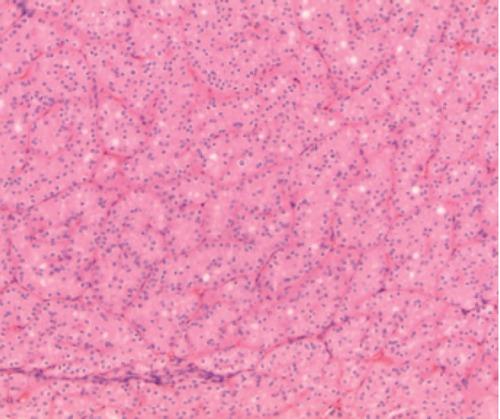

Renal oncocytomas are the most common benign solid renal tumor, accounting for 3-7% of renal neoplasms. Oncocytomas are multifocal in 2-12% and bilateral in 4-14% of cases. Multifocal bilateral oncocytomas represent only 1.4% of renal cases. We present an extraordinary case of a patient with multifocal bilateral renal oncocytomas during pregnancy. An electronic literature search revealed fewer than 30 reports of on cases of bilateral multifocal renal oncocytomas, none of them occurring in pregnancy. The management of this patient differed from the recommended guidelines for renal masses suspected to be malignant because elective caesarean section and nephrectomy in the second trimester was refused.

肾嗜酸细胞瘤是最常见的肾脏良性实性肿瘤,占肾肿瘤的3%至7%。2%至12%的病例中嗜酸细胞瘤为多灶性,4%至14%的病例为双侧性。多灶性双侧嗜酸细胞瘤仅占肾病例的1.4%。我们报告一例妊娠期多灶性双侧肾嗜酸细胞瘤的特殊病例。电子文献检索显示,双侧多灶性肾嗜酸细胞瘤病例报告少于30例,且均未发生在妊娠期。该患者的治疗与疑似恶性肾肿块的推荐指南不同,因为患者拒绝了孕中期选择性剖宫产和肾切除术。